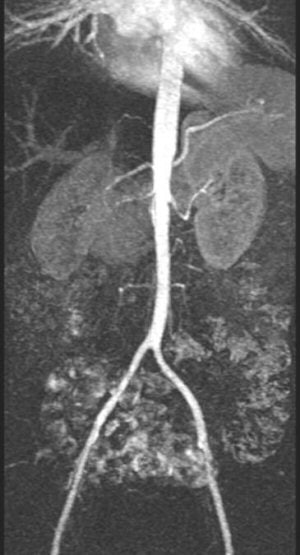

CT angiography (CTA) is ideal for imaging accessory renal arteries. And CTA with spiral and multidetector-row scanners provides better resolution compared to MR angiography (MRA). Maximum intensity projections (MIP) and volume-rendering algorithms can also be used to analyse the dataset (Radiology, May 1999, Vol. 211:2, pp. 337-343). CTA is also very useful in providing a road map for surgery because the 3D relationship of the vessels in the renal hilum can be visualised.

However, with CTA there is risk of contract-induced nephrotoxicity in patients with baseline renal impairment or diabetes. Taking this into consideration along with the risk from radiation, MRA may be a better choice for RAS. "MRA is emerging as the most important noninvasive imaging modality for stenosis," Moorthy said.

![]() |

| Contrast-enhanced MRA showing long-segment stenosis of the right renal artery. |

3D spoiled gradient-echo, gadolinium-enhanced breath-hold imaging is required for adequate visualisation of the renal artery. MRA studies for RAS have shown good results, with 97% sensitivity and 92% specificity for stenosis grading and detecting peripheral stenosis and accessory arteries (Radiology, February 2001, Vol. 218:2, pp. 481-490).